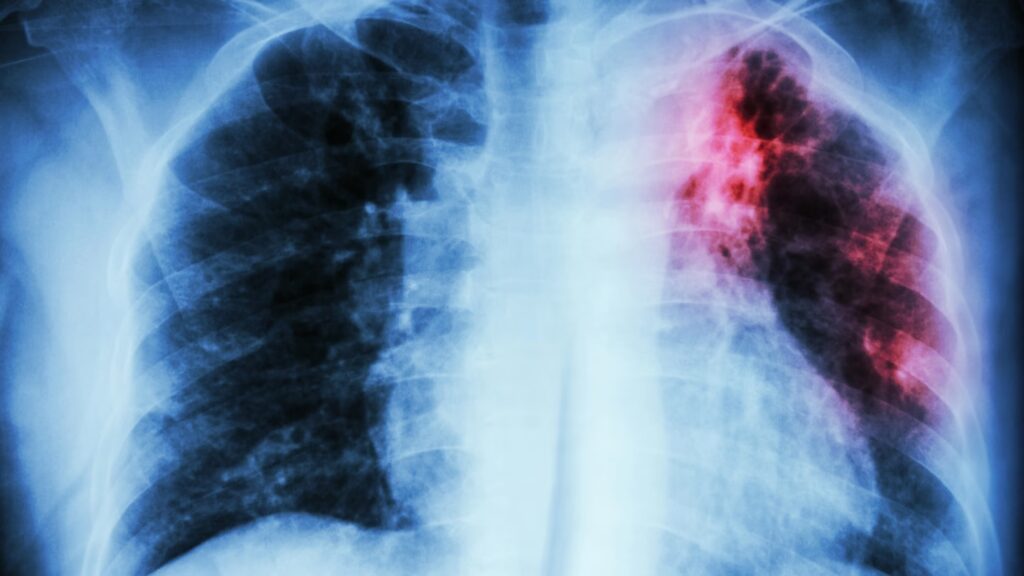

- Røntgenbillede af brystkassen: Hvis den indledende test er positiv, eller hvis der er stærk mistanke om aktiv sygdom, vil det næste skridt ofte være et røntgenbillede af brystkassen. Dette kan afsløre forandringer i lungerne, der er typiske for tuberkulose, såsom infiltrater eller kaverner (huller i lungevævet).